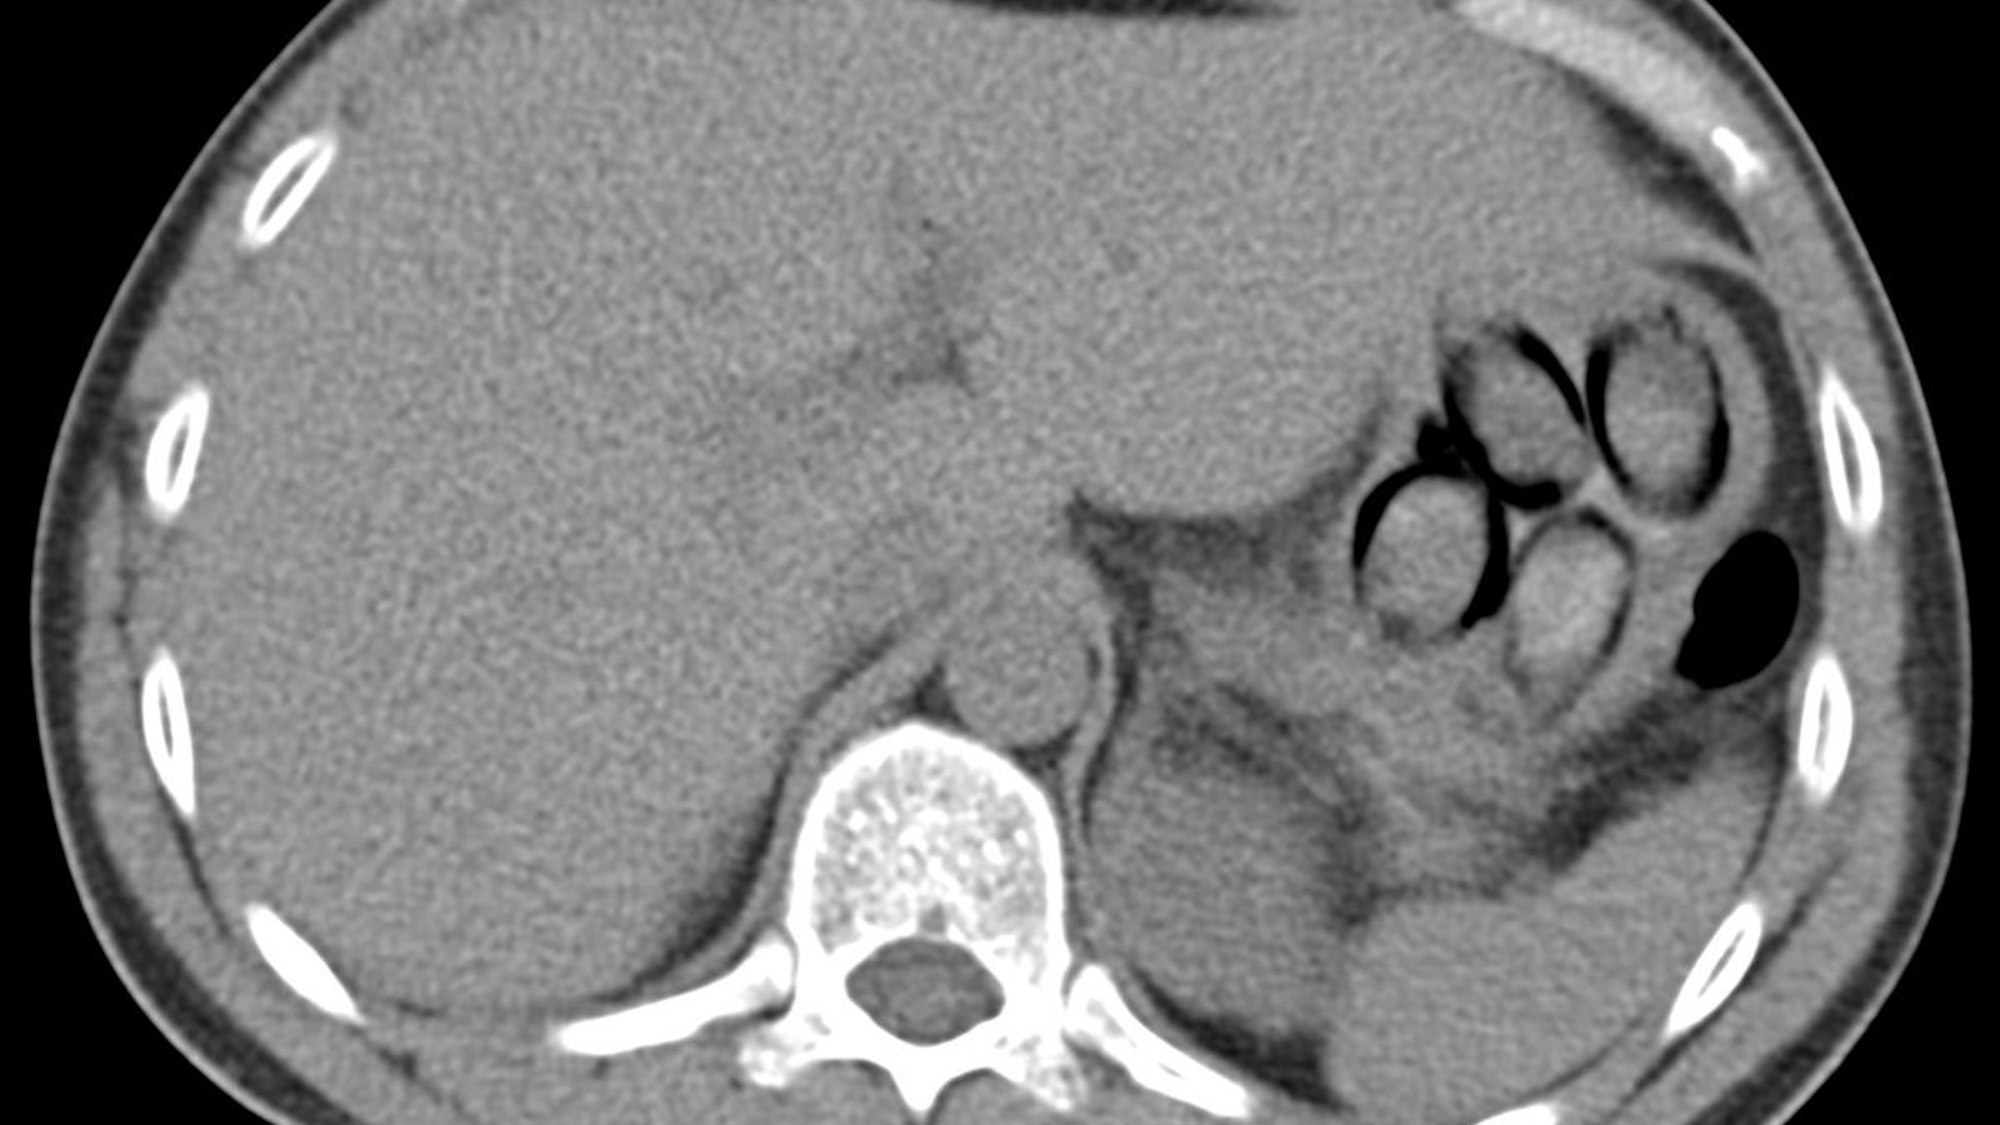

„Die Röntgenaufnahme in einem nahegelegenen Krankenhaus bestätigte letztendlich den Verdacht meiner Kolleginnen und Kollegen, denn im Magen des Mannes waren mehrere Drogenpäckchen klar zu erkennen. Insgesamt schied der Mann dann unter Überwachung sieben sogenannte Bodypacks mit insgesamt mehr als 100 Gramm Kokain aus“, berichtet Jens Ahland, Pressesprecher des Hauptzollamts Köln.